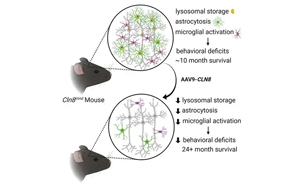

AAV9-DARS2基因療法治療LBSL:從患者細胞到小鼠模型的表型拯救與機制探索

來自多機構(gòu)的研究團隊針對由DARS2基因突變引起的罕見遺傳性白質(zhì)腦病LBSL,開發(fā)了AAV9介導的DARS2基因補充療法。研究證實該療法可顯著改善患者神經(jīng)元線粒體功能、促進軸突生長并降低乳酸水平,在小鼠模型中單次給藥6個月后仍能延緩神經(jīng)退行性病變,為臨床治療提供了關鍵實驗依據(jù)。